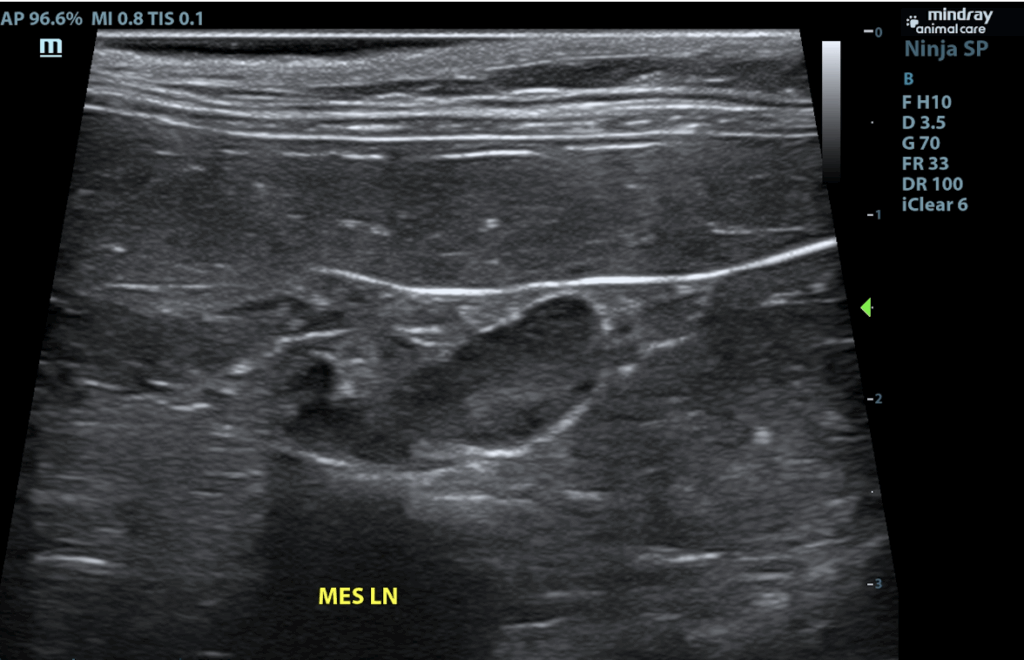

Mesenteric lymph nodes are prominent in size with swollen capsular contour. Normal elongated shape(length to width ratio) is maintained. There is no loss of parenchymal detail.

- Very mild reactive mesenteric lymph nodes – infiltrative neoplastic disease cannot be ruled out but is considered less likely.